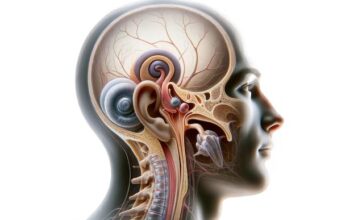

Discover the wonders of the human body, from its fundamental elements to the intricate systems that sustain life. This section explores the anatomy, physiology, and functions of various body parts, providing insights into our movements, thoughts, emotions, and interactions with our surroundings.